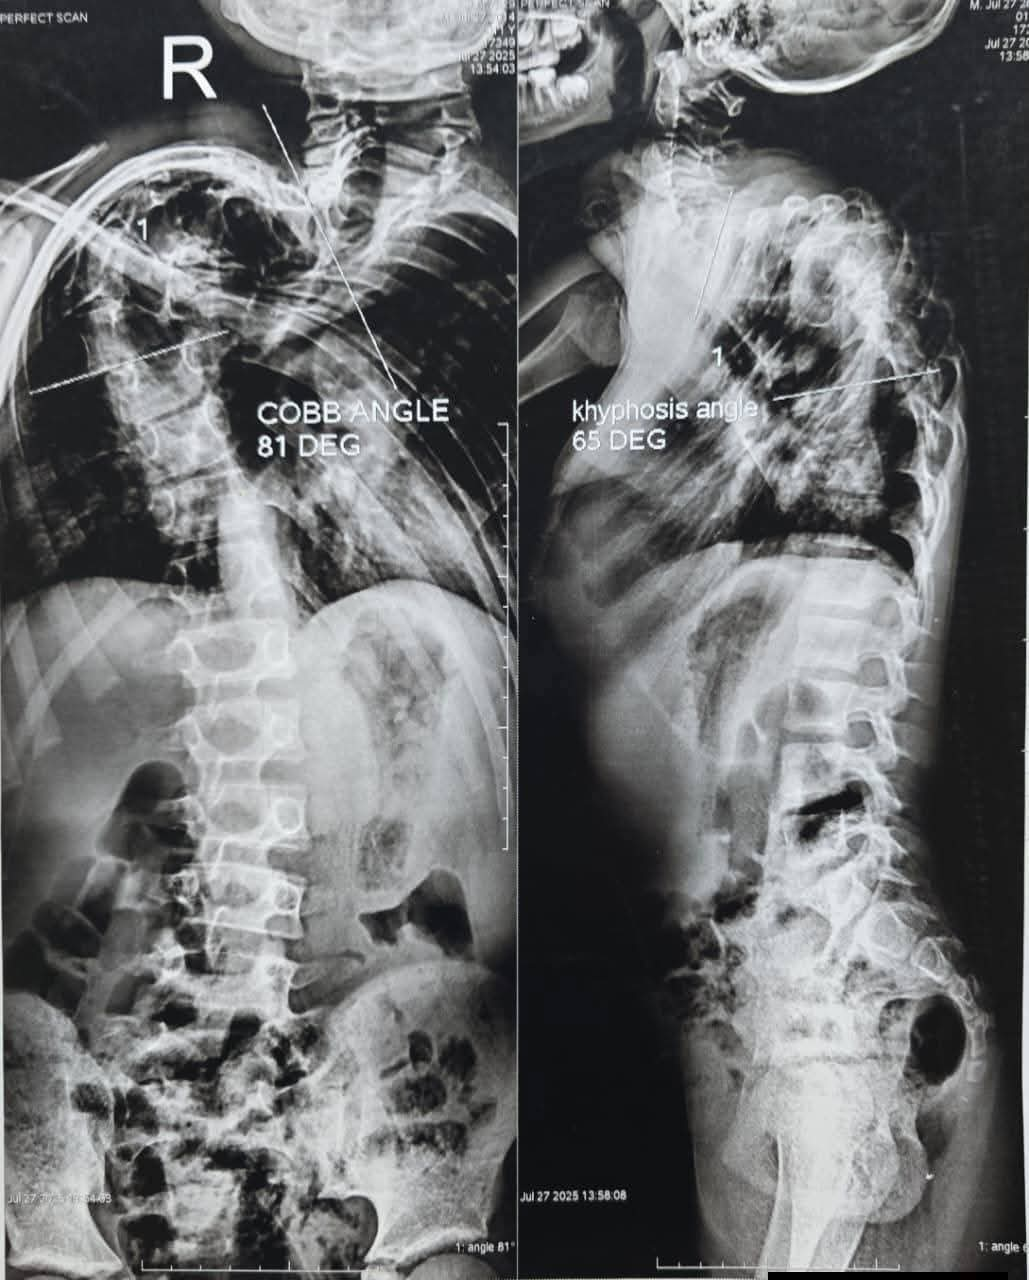

وقام الطفل محمد بالذهاب إلى أكثر من مستشفى ولكن دون جدوى؛ نظرًا لصعوبة العملية الجراحية التي تتطلب أكثر من متخصص لإجرائها، وقد حضرت أسرة المريض محمد إلى عيادة جراحة العظام بمستشفى الزهراء الجامعي، حيث كشفت الفحوصات الأولية عن وجود تشوه فقري كبير وسريع التطور، لدرجة أن المعالم التشريحية الطبيعية للفقرات لم تكن واضحة باستخدام الأشعة التقليدية، ما استدعى إجراء أشعة مقطعية ثلاثية الأبعاد، إلى جانب الاستعانة بتقنية الطباعة ثلاثية الأبعاد لتصنيع نموذج بلاستيكي مطابق للتشوه الحقيقي في العمود الفقري للمريض، بما أتاح تقييم الحالة بصورة علمية دقيقة، وساعد الفريق الجراحي على التشخيص والتخطيط السليم للتدخل الجراحي قبل إجراء العملية الجراحية.

وأظهرت الدراسات أن حجم وتعقيد التشوه يجعل من المستحيل إجراء جراحة تقويم تقليدية باستخدام المسامير بصورة آمنة أو فعالة، الأمر الذي تطلب إعداد خطة علاجية غير تقليدية تعتمد على التعاون بين وحدات تخصصية دقيقة داخل قسم جراحة العظام، حيث استدعت الحالة ضرورة اللجوء إلى الشد المحوري الرأسي التدريجي للعمود الفقري؛ لإظهار معالمه التشريحية، وإتاحة الفرصة لإجراء الجراحة التصحيحية النهائية لاحقًا.

وبعد مرور ثلاثة أشهر من الشد التدريجي باستخدام المثبت الخارجي ذي التقنية المتخصصة أُجريت الجراحة النهائية التي تضمنت تصحيحًا كبيرًا لتشوه العمود الفقري وتثبيت الفقرات باستخدام المسامير الفقرية والأعمدة المعدنية، وذلك تحت مراقبة جهاز متابعة الأعصاب أثناء الجراحة.